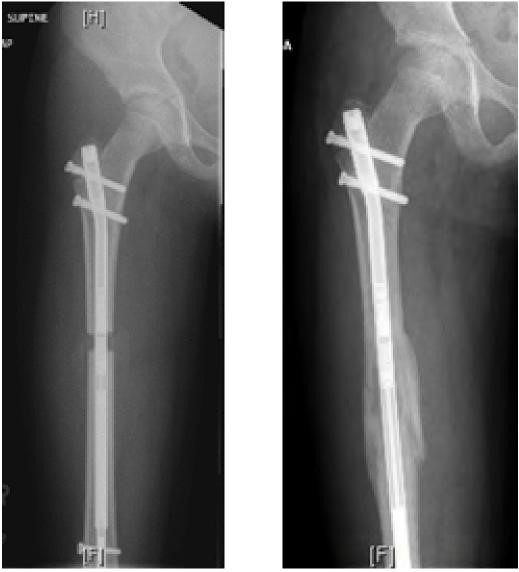

Since then, there have been numerous innovations in circular external fixator limb lengthening devices. Most recently, we have performed the first magnetic limb lengthening using the PRECICE nail in our region. This is an intramedullary rod that has a magnetic actuator drive that uses an external electromagnetic actuator to control rate and direction of lengthening, thus eliminating the need of external fixation (Figure 5).

Despite a 5.0 cm lengthening, her LLI continued to progress and by age 10 years, 2 months, she had a discrepancy of 8.0 cm. We then did a PRECICE Femoral Nail, lengthening her magnetically an additional 6.0 cm (Figure 7).

She has regained full motion and function from her intramedullary limb lengthening having lengthened her right leg a total of 11.0 cm. We used a combination of two limb lengthening techniques, using an external fixation done on her tibia thus avoiding her growth plates. Magnetic intra-medullary lengthening can only be used in children over 10 years as the width and length of the rods are limiting factors.